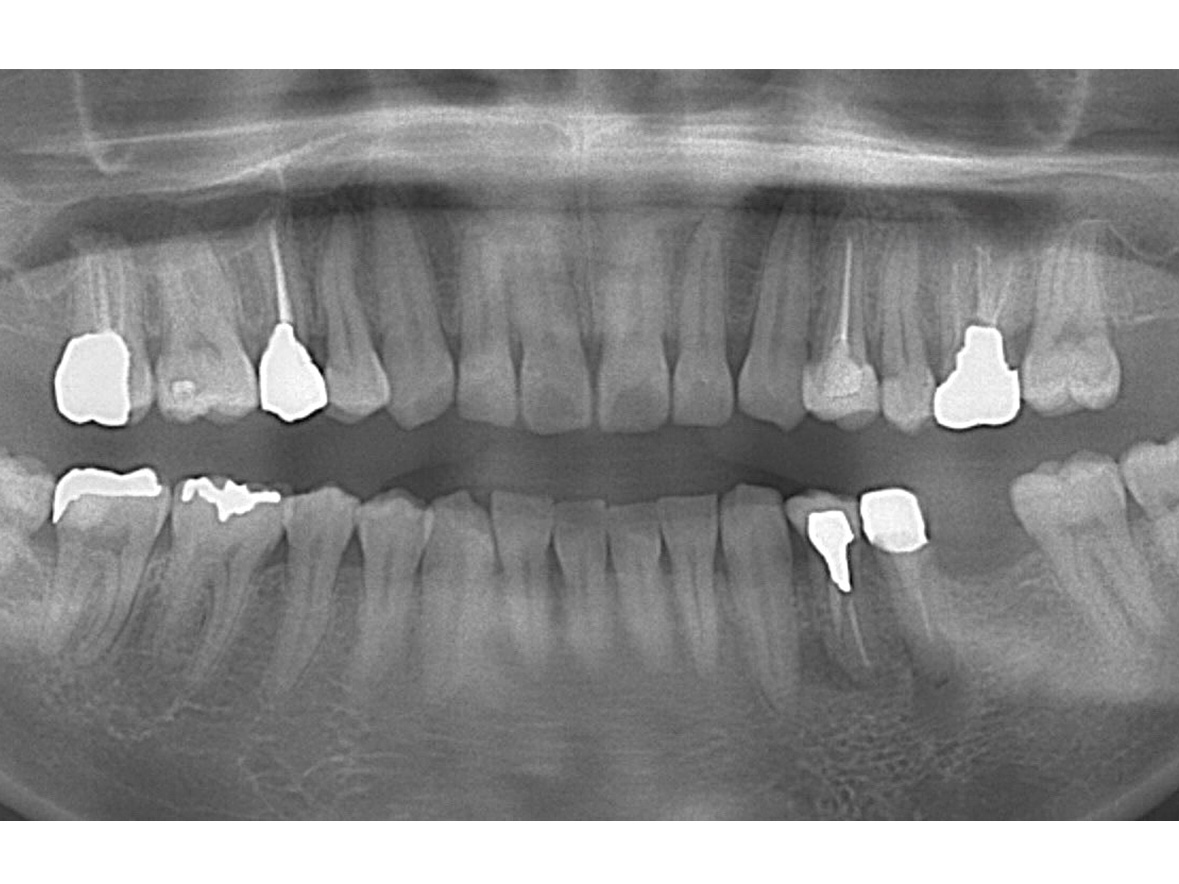

症例3

患者様の年齢 60代男性 主訴 歯が痛い 治療内容 左下456インプラント治療

抜歯即時インプラント埋入後3ヶ月の待機期間後、ジルコニアによる上部構造装着費用 77万円 治療期間・通院回数 4ヶ月/5回 デメリット・リスク 外科処置に伴う痛み・腫れ・出血・合併症の可能性があります。 -